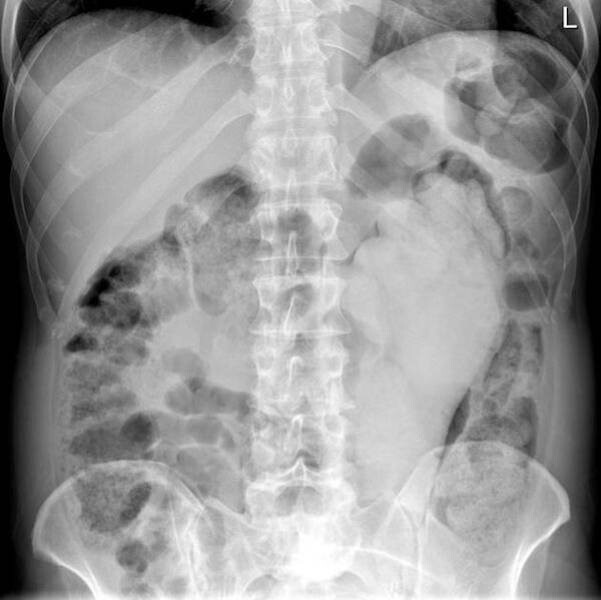

Лікарі-рентгенологи та хірурги за свою багаторічну практику бачать багато чого дивовижного та несподіваного.